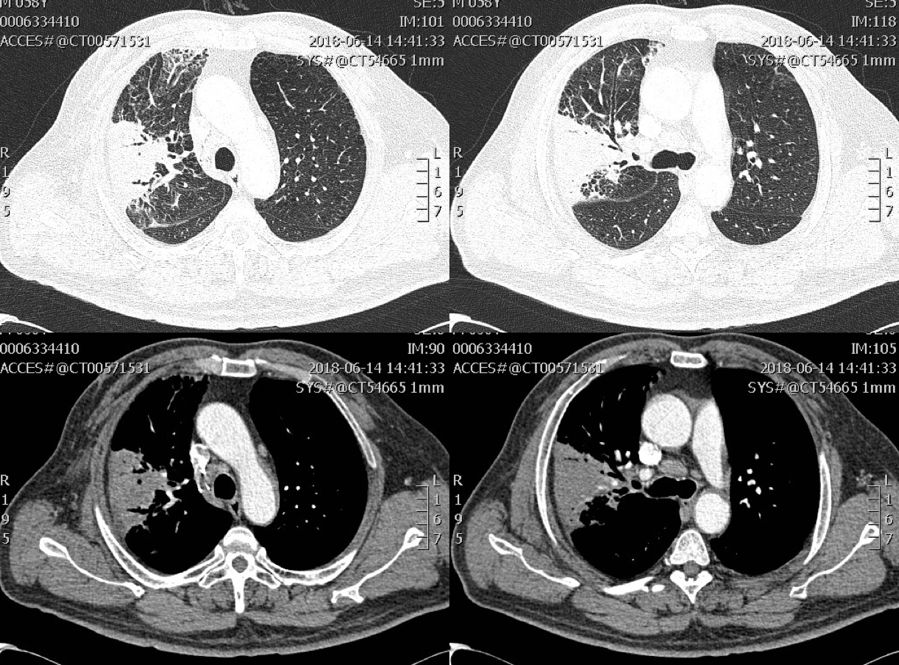

58岁男性患者,诊断慢阻肺3年。因反复咳嗽咳痰气促3年,再发加重伴咯血1+月入院。

体查:体温:36.0℃,脉搏:87次/分,呼吸:20次/分,血压:166/104mmHg;慢性病容,桶状胸,双侧呼吸动度对称,语颤无增强,双肺叩诊过清音,双肺呼吸音粗,右上肺少许干罗音,双肺未及胸膜摩擦音。

肺部CT:右上肺渗出

支气管镜:双肺支气管炎症改变,右上叶前支靠后亚分支见黄色脓栓,余1-4级支气管内可见少许脓性分泌物。

• 血象正常,ESR 70mm/h ↑, CRP 19mg/L↑ ,PCT 0.14ng/ml ↑,多次病原学检查、支气管灌洗液检查阴性。

• 病理:炎性支气管粘膜组织及肺组织,灶性肺泡上皮增生活跃,间质纤维增生及玻变,较多淋巴细胞、浆细胞混有粒细胞浸润,免疫荧检查真菌(+),PSA染色见个别可疑真菌菌丝,考虑真菌感染可能性大。

• 最终诊断:慢阻肺合并侵袭性肺曲霉病

• 予伏立康唑6mg/kg(首剂)4mg/kg静滴Q12H(维持)抗真菌以及止血对症治疗,患者好转出院序贯口服治疗。